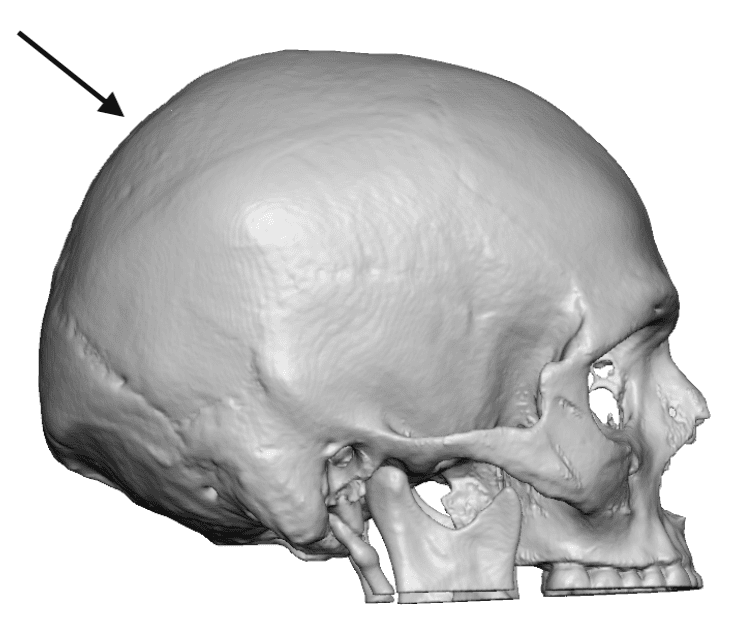

Patient 21

Desire for reduction of prominent posterior sagittal crest of bone.